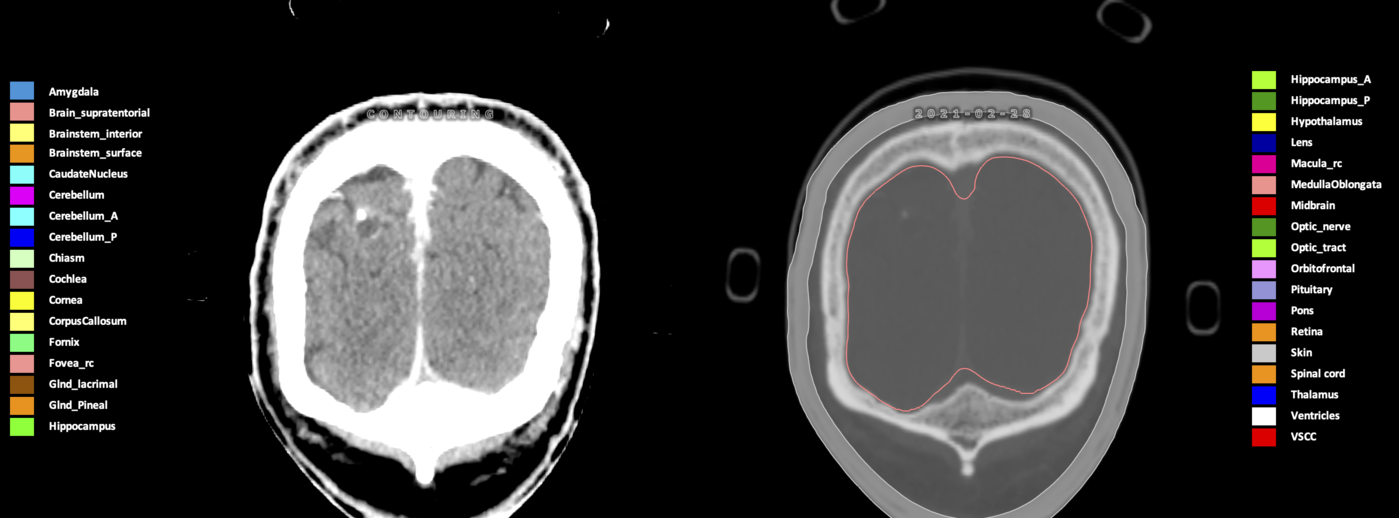

Included are all OARs known to be relevant for radiation-induced toxicity in neuro-oncology: brain, brainstem (midbrain, pons, medulla oblongata), chiasm, cerebellum (anterior & posterior), cochlea, cornea, hippocampus (anterior & posterior), hypothalamus, lens, lacrimal gland, optic nerve, pituitary, skin, and vestibular & semicircular canals. To further facilitate research on cognition, vision and radiological changes after irradiation of the brain, potential clinically-relevant OARs are included: amygdala, caudate nucleus, cerebellum (anterior & posterior), corpus callosum, fornix, macula, optic tract, orbitofrontal cortex, periventricular space (PVS), pineal gland, and thalamus.

Three-dimensional delineation of the 25 consensus OARs for neuro-oncology are shown on CT (WW/WL 120/40, 3000/600), 3T MR images, (T1Gd, T2FLAIR 1mm) and 7T MR (MP2RAGE 0.7 mm). All are presented in transversal, sagittal and coronal view.